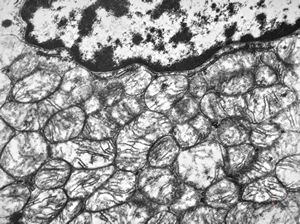

F, 72y. | carcinoid … metastasis to lymphonode